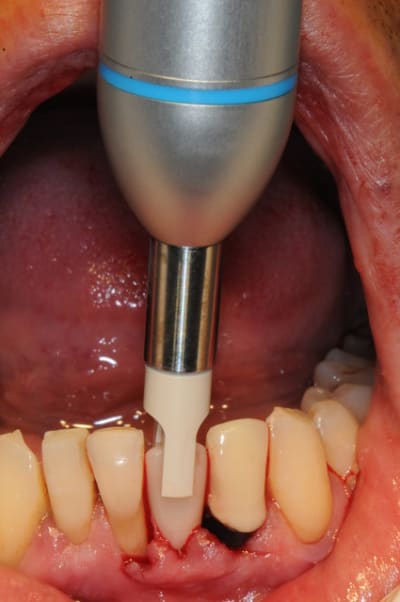

7)8) on met l'implant avec ses petits didis

9)10)11) implant in situ

15)16)17)18)19) jour zéro (dent en sous occlusion)